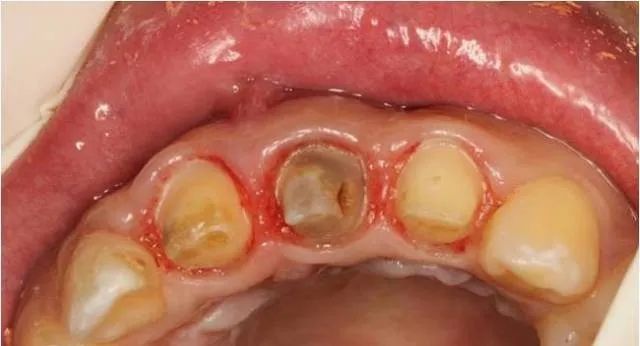

基牙备置

临时冠修复

术后两周拆线后口内情况

三个月后修复牙体制备后